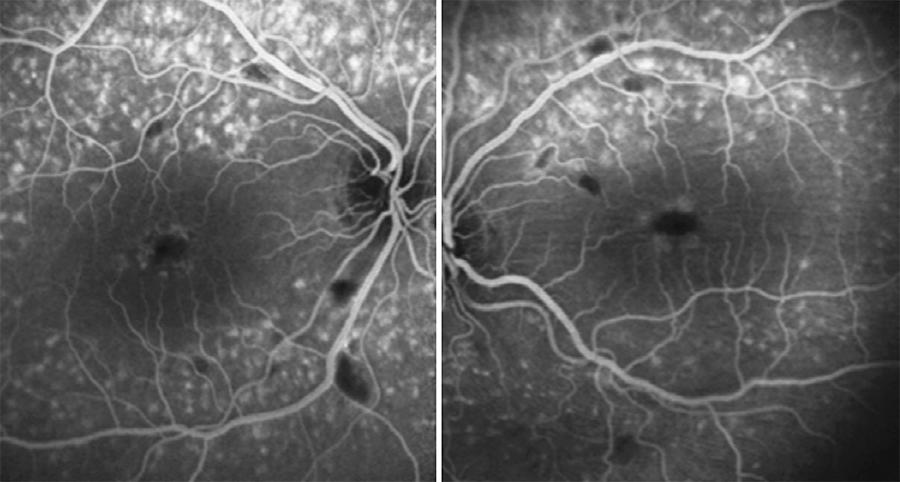

Fluorescein angiography (FA) was performed, which showed lack of perfusion areas by capillary closure coinciding with the cotton wool spots and pigmentary changes surrounding both foveas. An optical coherence tomography (OCT) examination of the macula revealed the presence of hard exudates in the outer plexiform layer of both eyes, and an epiretinal membrane (EM) in the left eye, possibly associated with exudative retinal microangiopathy secondary to the use of IFN (Figures 2 and 3).

Figure 2 FA of the patient, where a lack of perfusion areas by capillary closure coinciding with cotton wool spots are shown.